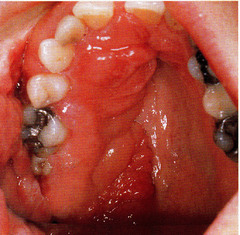

-mucosa surfaced by multiple erythematous papillary projections on hard palate -cause: constant wearing of maxillary prosthesis